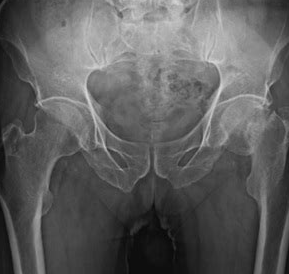

| 인공고관절 수술 | 고관절염, 골절 치료를 위해 손상된 관절을 인공관절로 대체 |

| 비구 성형술 | 고관절 이형성증 치료를 위해 골반 성형 |

고관절 수술은 주로 노화나 사고로 인해 손상된 관절을 복원하기 위해 시행됩니다. 환자의 상태에 따라 맞춤형 접근이 필요합니다.